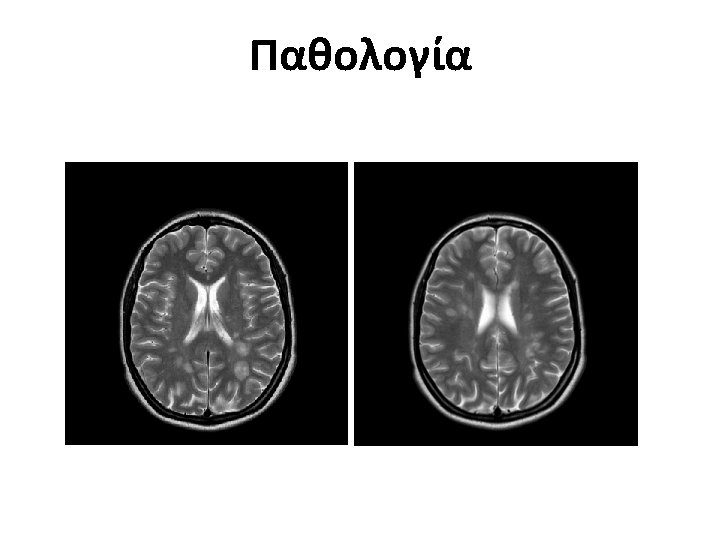

Multiple Sclerosis • Multiple Sclerosis (MS) is a chronic inflammatory demyelinating and degenerative disease of the Central Nervous System (CNS) affecting both the Brain and the Spinal Cord.